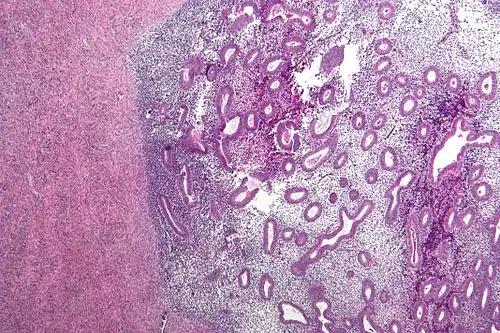

For a histopathological diagnosis, at least two of the following three criteria should be present:[121]

- Endometrial type stroma

- Endometrial epithelium with glands

- Evidence of chronic hemorrhage, mainly hemosiderin deposits

Immunohistochemistry is useful in diagnosing endometriosis as stromal cells have a peculiar surface antigen, CD10, thus allowing the pathologist go straight to a staining area and confirm the presence of stromal cells and sometimes glandular tissue is identified that was missed on routine H&E staining.[122]

Micrograph showing endometriosis (right) and ovarian stroma (left) -

Micrograph of the wall of an endometrioma. All features of endometriosis are present (endometrial glands, endometrial stroma and hemosiderin-laden macrophages).